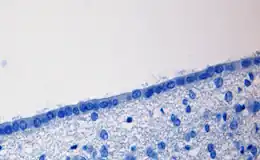

La description histologique des cellules épendymaires est très variable selon leur localisation anatomique. Elles présentent une forme grossièrement cuboïde avec une partie basale et une partie apicale (ou ventriculaire). La surface ventriculaire est pourvue de cils mobiles.

Les cellules épendymaires sont dépourvues de lame basale et ne présentent pas de jonctions serrées (à la différence de nombreux épithéliums) entre le liquide cérébrospinal et le tissu nerveux. Les cellules épendymaires ne forment donc pas, stricto sensu, un épithélium (le terme de « pseudo-épithélium » serait plus adéquat). Néanmoins, on pourra distinguer les épendymocytes des plexus choroïdes qui forment un épithélium, des épendymocytes des plexus extrachoroïdes, qui eux forment un pseudo épithélium.

Les cellules épendymaires sont unies entre elles par des jonctions latérales (zonula adhaerens) et en particulier des jonctions communicantes. Cette couche cellulaire ne forme pas une barrière imperméable (pas de zonula occludens, excepté au niveau des plexus choroïdes) mais sa perméabilité est régulée en particulier grâce aux aquaporines (canaux transporteurs d'eau).